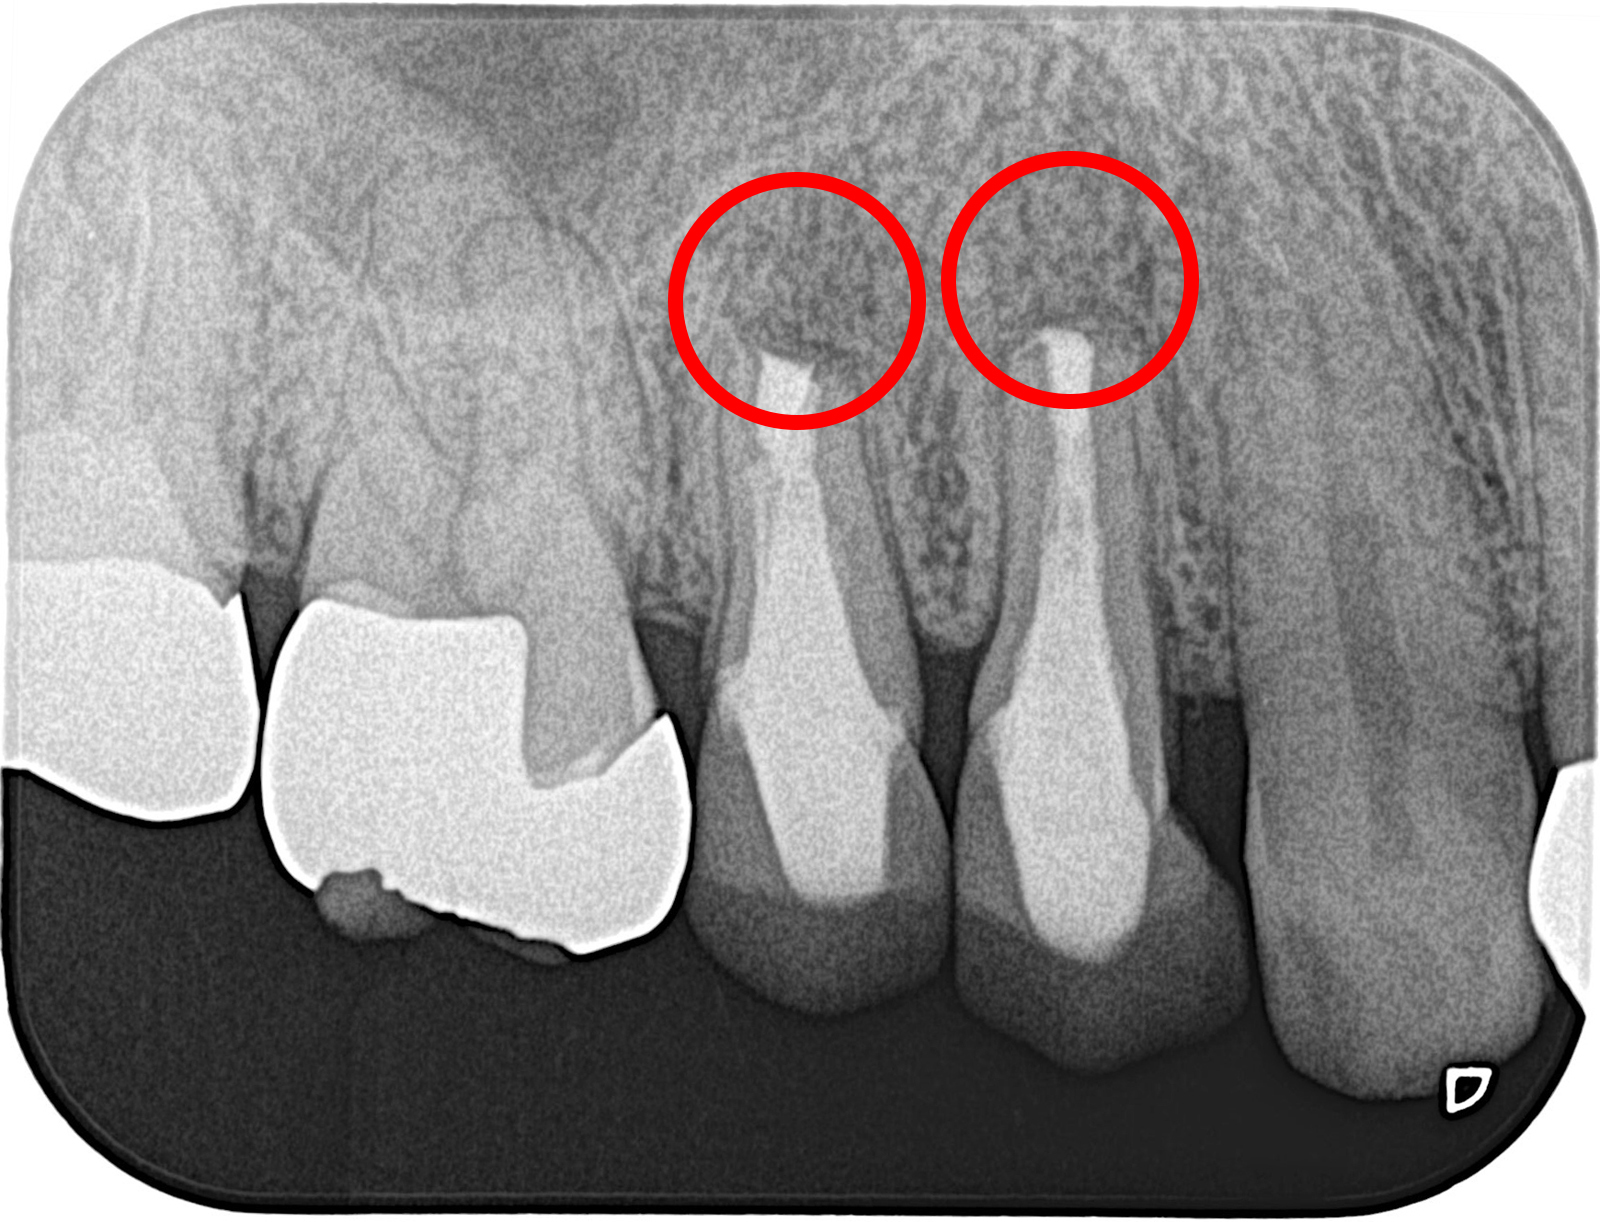

他院で根管治療を受けたが痛みが取れず、当院で歯根端切除を行った。

術後8カ月、きれいに骨が再生している。